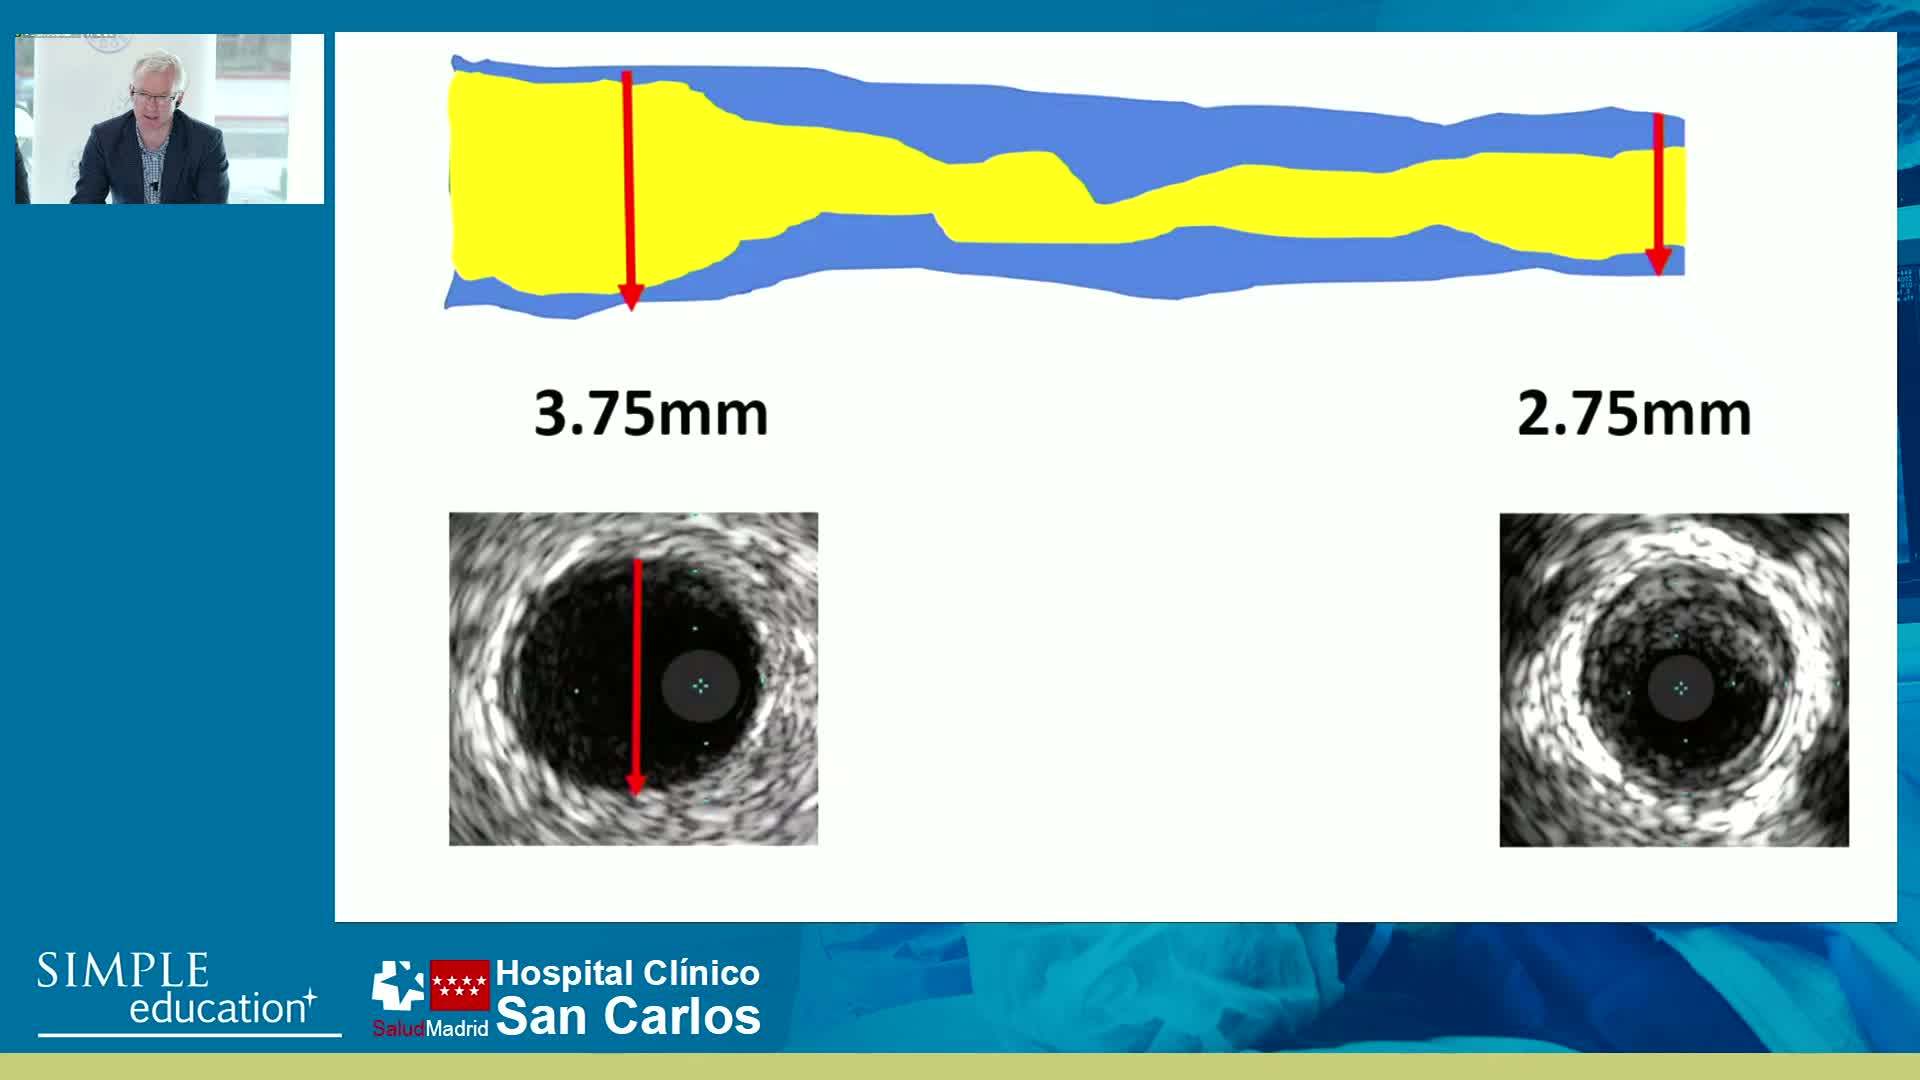

How to perform good co-registration measurements using iFR and IVUS - Prof Carlo Di Mario

Essential steps for physiology-based PCI planning and guidance - Dr Allen Jeremias

Best practices and personalised medicine in complex PCI - Prof Javier Escaned